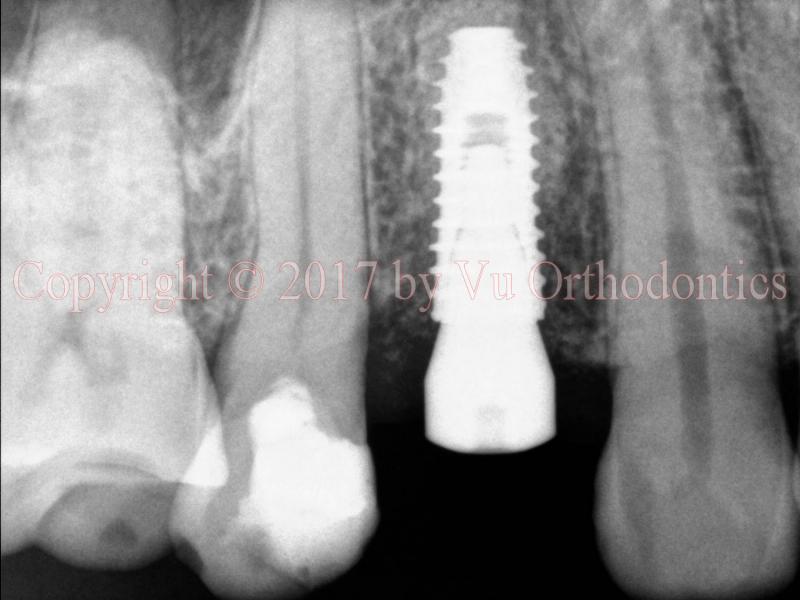

Another case of bad implant placement (which was done elsewhere) is shown in Fig. 3 (photo) and Fig. 4 (cross-sections of the CBCT scan). In this case, the implant is almost completely out of the bone. The site is of the upper right second premolar (Tooth #4). Even if the dentist had placed the implant in a perfect position and orientation, the bone width (in buccal-palatal direction) would still have been too small for this implant (6.22 mm, measured at the implant-platform level). According to the patient, the dentist who placed three (3) implants on him. But two (2) fell out, and only one remains. The dentist took some radiograph(s), presumably, PA or BW or both, and then told the patient, "The bone looks good."

Fig. 3. Implant for Tooth #4 site is outside of the bone and protruding under the soft tissue (photo)